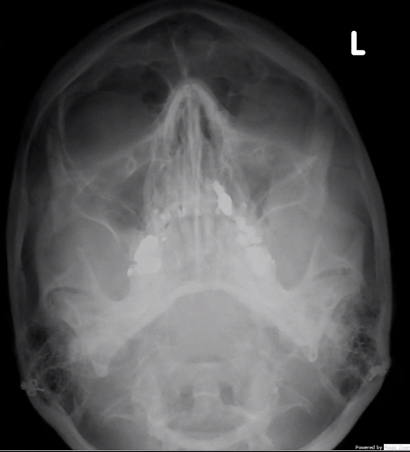

LeFort I

horizontal fracture of maxilla

least amount of force to cause fracture

LeFort II

pyramidal horizontal

fracture of maxilla and nose

LeFort III

craniofacial disjunction

bone is not stabilized and is mobile

face not attached to cranium

fracture near orbits

least common injury, with extreme force needed to occur